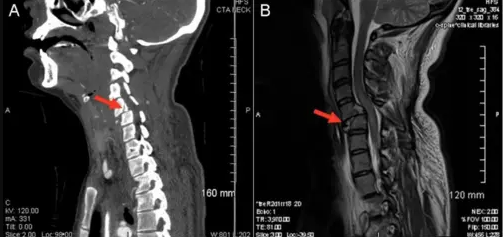

A 25-year-old woman was a restrained driver in a rollover motor vehicle accident (MVA) and suffered a C5-C6 fracture-dislocation with spinal cord injury. She developed neurogenic stunned myocardium and neurogenic shock. Her unopposed parasympathetic nervous system triggered multiple episodes of unstable bradycardia which resulted in multiple cardiac arrests. She was treated with inotropes and vasopressors to keep her mean arterial pressure (MAP) > 85 mmHg for adequate spinal perfusion. Chronotropic medications were used to elevate her heart rate (HR) in order to prevent her unstable bradyarrhythmia from causing a cardiac arrest.